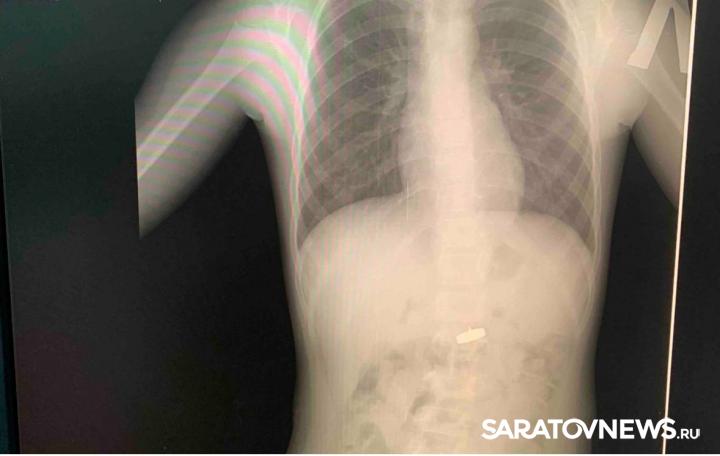

В Энгельсе 5-летняя девочка проглотила магнит с шурупом. Об этом сообщает в своем телеграм-канале министр здравоохранения Саратовской области Олег Костин.

Ребенка доставили в 1-ю городскую клиническую больницу, где врачи с помощью эндоскопического зажима «сачок» за три минуты извлекли инородное тело.

От магнита и острого шурупа в желудке у несовершеннолетней образовались геморрагические эрозии. Поэтому в данный момент ребенок продолжает лечение в больнице.